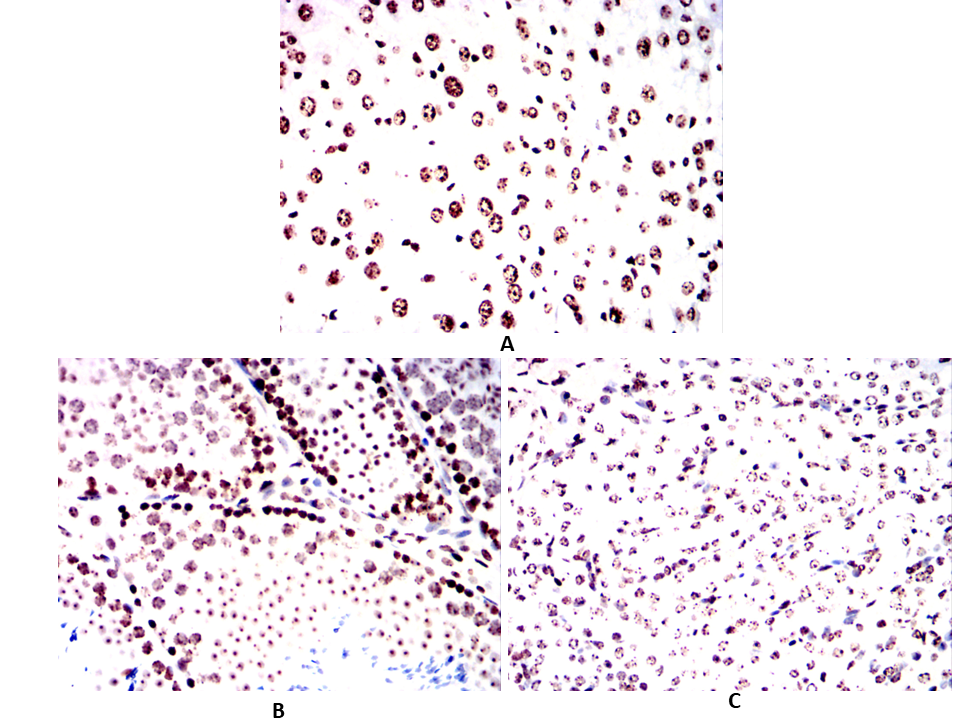

| IHC | 1/100 - 1/500 | Human,Mouse,Rat,Rabbit |

Antibodies targeting p16 are essential tools in both research and diagnostics. Mouse- and human-specific p16 antibodies enable the detection of p16 expression across species, facilitating comparative studies in preclinical models (e.g., murine systems) and human tissues. These antibodies are widely used in techniques such as immunohistochemistry (IHC), Western blotting, and immunofluorescence to assess p16 status in tumors, senescent cells, or disease models. In clinical settings, p16 immunohistochemistry serves as a surrogate marker for high-risk human papillomavirus (HPV) infection in cervical and head/neck cancers, aiding diagnosis and prognosis.